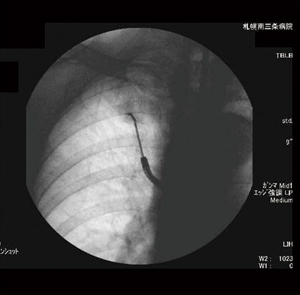

特定した病変内の気管支の断端を始点とし,気管分岐部の上部の終点まで気管支の走行のパスを作成した。CPRでプロットしたパスラインが3D画像上で二次元的に表示されるので,3D画像をレイサム画像(図2)で表示すると,透視下で行うTBLB施行時の鉗子などの位置を把握できる画像(図3)と同じように表現できた。

図3 透視画像 |

検査施行時,透視画像でしか確認できない現状では,鉗子などを挿入している気管支を正確に判断することが困難であることも多い。透視画像は二次元のデータであり,奥行きの情報を持たない。患者のlateral方向の情報がほしいときには,管球が回転するタイプの透視装置でなければ,気管支鏡を挿入されている患者自身に体位を変えてもらうしかないが,それは大変な困難を伴うことが多い。